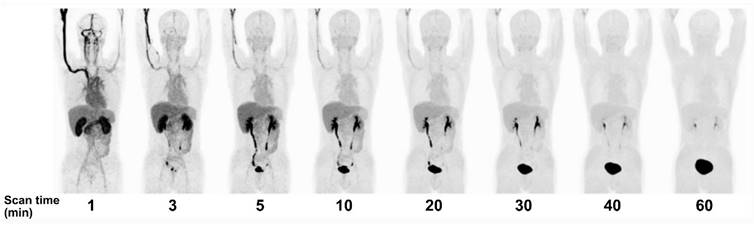

Figure 4

PET MIP images over time after [18F]FBY administration in a healthy volunteer. Adapted with permission from [74]. Copyright © 2021, The Author(s), under exclusive license to Springer-Verlag GmbH, DE, part of Springer Nature.

Since June 2020, BNCT has been covered by national insurance in Japan for head and neck cancer. Thus, we may expect a wider use of [18F]FBPA PET. Meanwhile, Li et al. in China developed [18F]trifluoroboratetyrosine ([18F]FBY) as an alternative for BPA and [18F]FBPA (Figure 1) [73]. The reason was twofold: 1) in vivo deboronation of [18F]FBPA and 2) the distinct molecular structure between BPA and [18F]FBPA due to additional [18F] on the [18F]FBPA side chain. Both reasons contributed to the off-target irradiation during BNCT. The [18F]FBY unique radiolabeling approach replaces the amino acid carboxyl group with a negatively charged trifluoroborate group, allowing for quick radiolabeling (15 min) with favorable yield (~50%), radiochemical purity (~98%), and stability (4 h). [18F]FBY has molecular electrostatic potential, structure, and chemical characteristics similar to BPA and is metabolically more stable than BPA. Despite no information regarding LAT1 selectivity (in comparison to LAT2), their in vitro and animal studies showed that boron concentration in tumor, muscle, and brain (therapeutic dose of FBY) is highly correlated with the mean SUV of [18F]FBY in those regions. In humans, [18F]FBY PET images presented a rapid kidney clearance, resulting in an extremely low background uptake at 60 min post-injection (Figure 4) [74]. Preliminary PET studies in primary brain tumors and brain metastases showed very promising potential of [18F]FBY (T/N ratio at least 17.1 and 20.2, respectively [75] and better brain tumor lesions delineation than contrast-enhanced MRI [76]).